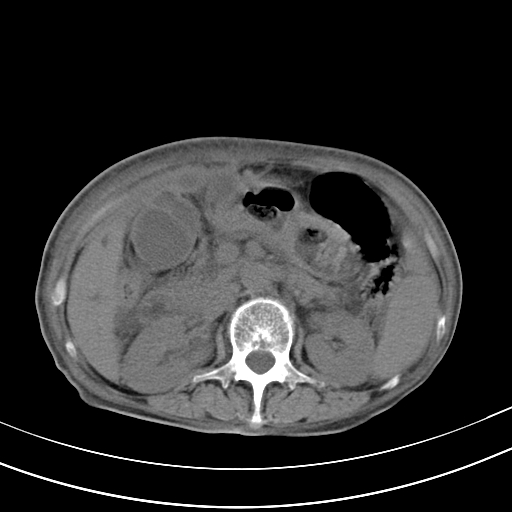

病人上腹部胀痛拌全身黄染八天

结石好象不明显吧?胆管稍扩张。

右侧少量胸水,胆囊增大,肝内胆管扩张,肝门部结构杂乱,建议增强。

肝内胆管及胰管扩张考虑为胰头区占位,肝门淋巴结增多,肝内多发低密度影,考虑为转移。门脉高压,脾大,胆囊大。

肝内胆管及胰管扩张,胰头增大考虑为胰头区占位,肝门淋巴结增多,考虑为转移。建议增强,脾大,胆囊大,壁厚,慢性胆囊炎。胃壁好像也增厚,且有一肿物。

1)考虑胰头癌并胆系低位梗阻;建议行ct增强扫描检查。2)慢性胆囊炎。3)脾大。4)少量腹水。5)双侧少量胸腔积液。